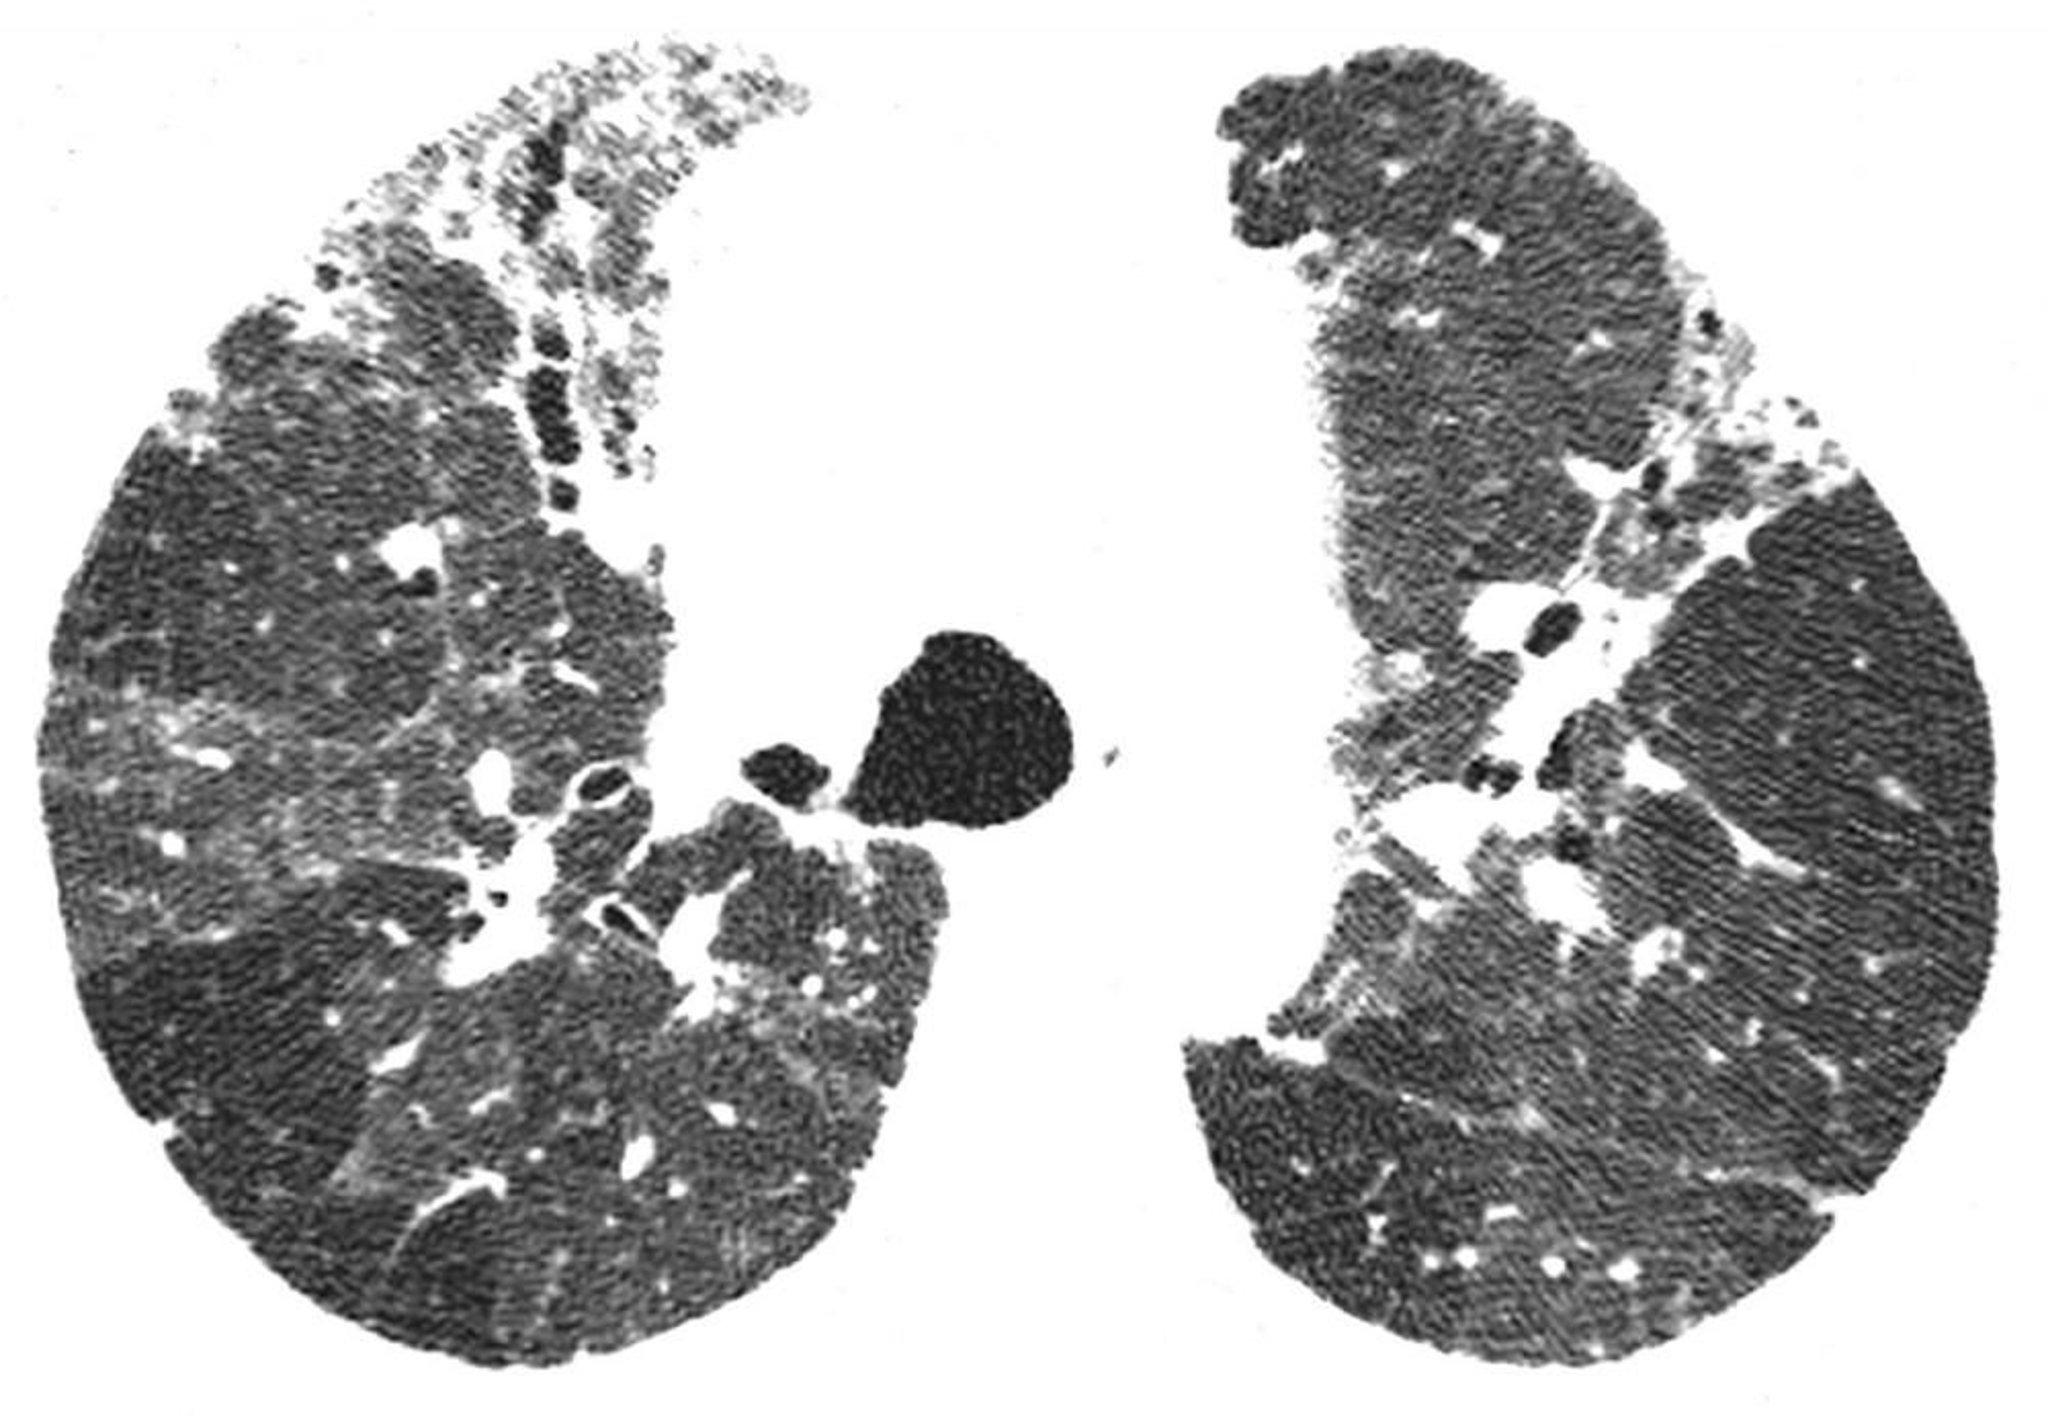

Chronische Hypersensitivitätspneumonitis

Die hochauflösende CT zeigt Befunde einer Fibrose, einschließlich unregelmäßiger Retikulation und Traktionsbronchiektasie. Bereiche mit verminderter Lungendichte sind kompatibel mit Regionen mit Atemwegsobstruktion. Diese Kombination von Befunden deutet auf eine Hypersensitivitätspneumonitis hin.

Image courtesy of Harold R. Collard, MD.